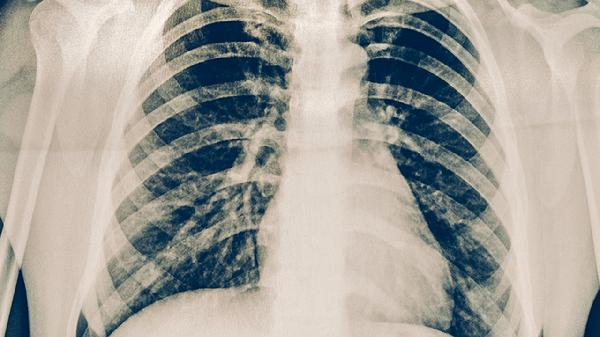

肺结核的手术治疗方式主要有肺叶切除术、全肺切除术、胸廓成形术、空洞引流术和淋巴结清扫术。肺结核通常由结核分枝杆菌感染引起,当药物治疗效果不佳或出现严重并发症时,可考虑手术治疗。

肺叶切除术适用于病灶局限于一叶肺且药物难以控制的患者。手术通过切除病变的肺叶来清除结核病灶,有助于控制感染和防止扩散。术后患者需要充分休息,并继续遵医嘱进行规范的抗结核药物治疗,以彻底治愈疾病。

全肺切除术用于病变广泛累及单侧全肺或伴有严重毁损肺的患者。该手术范围较大,旨在彻底移除病灶,但术后对肺功能影响显著。患者术后需密切监测呼吸功能,并进行呼吸康复训练,同时严格遵循医嘱完成抗结核治疗疗程。

手术治疗是肺结核综合治疗的一部分,通常在其他方法效果不理想时考虑。术后患者应注意休息,保证充足营养,摄入富含优质蛋白和维生素的食物如鸡蛋、瘦肉、新鲜蔬菜水果等,避免劳累和受凉。严格遵医嘱完成全程、足量的抗结核药物治疗至关重要,不可自行停药或减量。定期到医院复查胸部影像学和痰菌检查,监测病情变化。保持良好的生活习惯,戒烟限酒,有助于身体康复和预防复发。